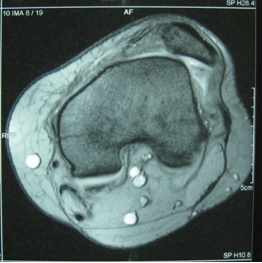

Operative Behandlung der Patellaluxation (MPFL-Rekonstruktion, Trochleaplastik)

Bei der sogenannten rezidivierenden Patellaluxation gibt es verschiedene operative Maßnahmen, die dazu führen, dass die Patella nicht mehr luxieren und dabei den Knorpel schädigen kann.

MPFL-Rekonstruktion (dabei wird mit einer körpereigenen Sehne – ähnlich wie bei der Ersatzplastik des vorderen Kreuzbands – das mediale patellofemorale Ligament, ein Halteband der Patella, rekonstruiert und meist mit einer sich selbst auflösenden Schraube fixiert)

Medialisierung der Tuberositas tibiae

Trochleaplastik (bei hochgradiger Trochleadysplasie kann eine knöcherne Rekonstruktion der Gleitrinne notwendig sein).